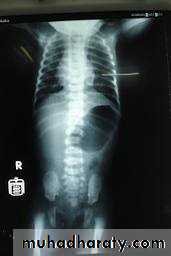

Infantile type :

Usually affect liver, spleen and pancreas , Incompatible with life .I.V.U.

- Bilateral Large kidney due to numerous small cysts (1-2 mm size ).- The out-line is not lobulated as in adult.

- I.V.U, may be normal.

- Nephrogram shows minute filling defects.